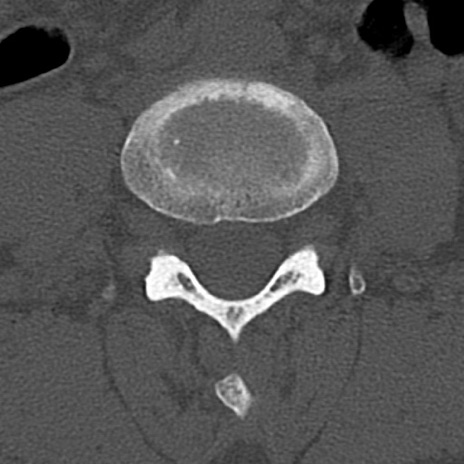

腰椎CT

横断像と矢状断像